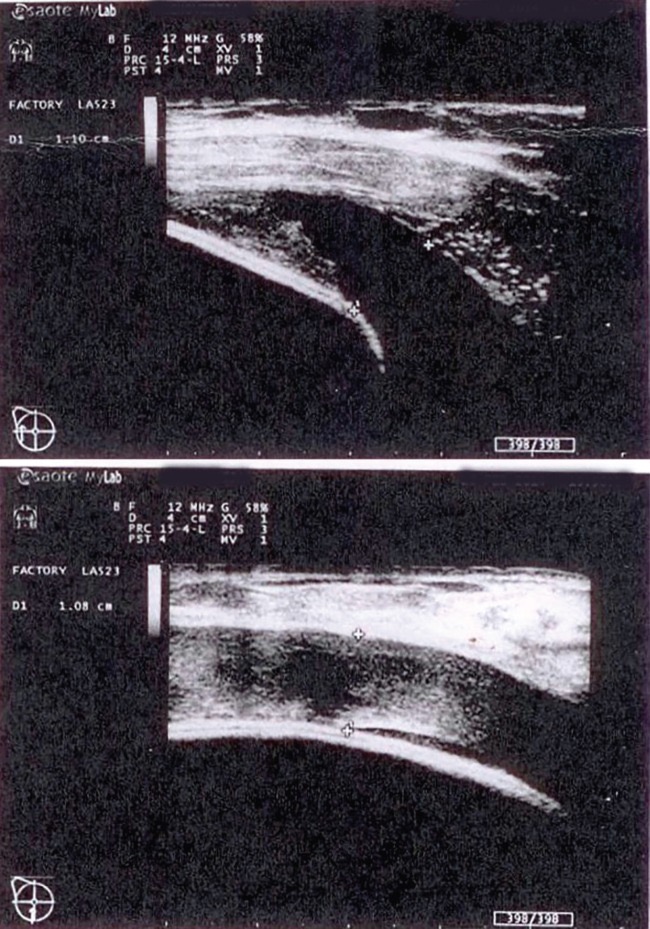

НемедицинаПо УЗИ вокруг имплантата скопилась неоднородная полоска жидкости шириной 2,5 см фото3. Общий анализ крови показал повышенное количество лейкоцитов, а эритроциты и гемоглобин были на нижней границе нормы. Имплантат был цел. Коагулопатий не обнаружено.